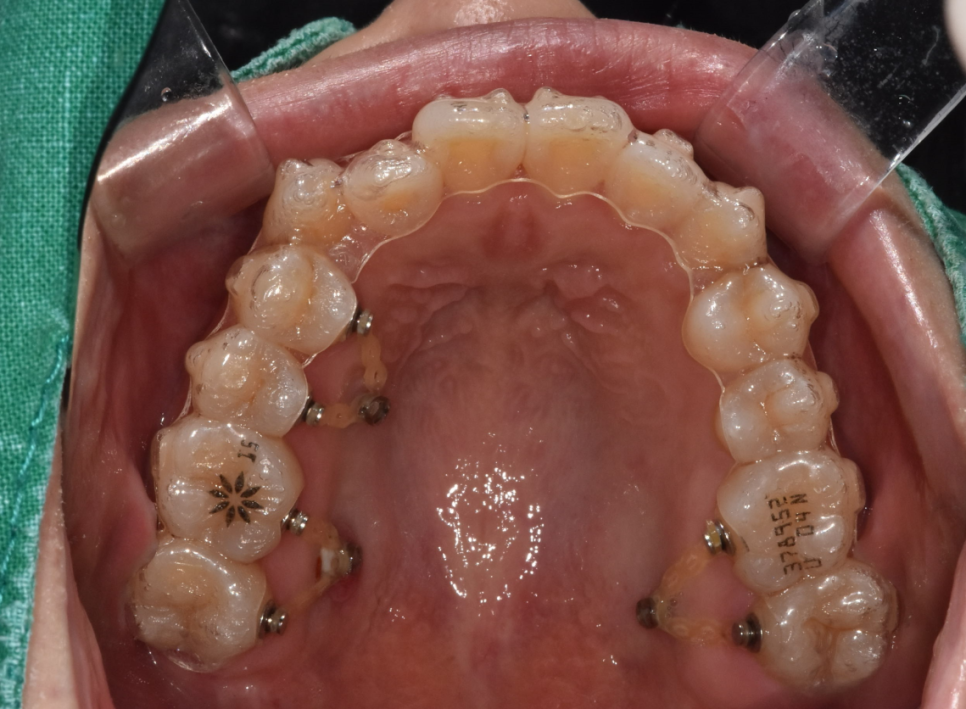

투명교정장치 착용 하루 20시간 이상 필수!

선택이 아니라 필수입니다.

사실상 밥을 먹고 양치를 하는 시간을 제외하고는

계속 끼고 있어주어야하는거죠 ~

하루에 20시간 정도는 끼고 있어주어야

치아를 지속적으로 움직이도록 만들어줍니다.

교정 장치가 입 안에 머무르는 시간이 부족하면

치아 이동이 늦어지고

치료 종결 역시 늦어집니다.